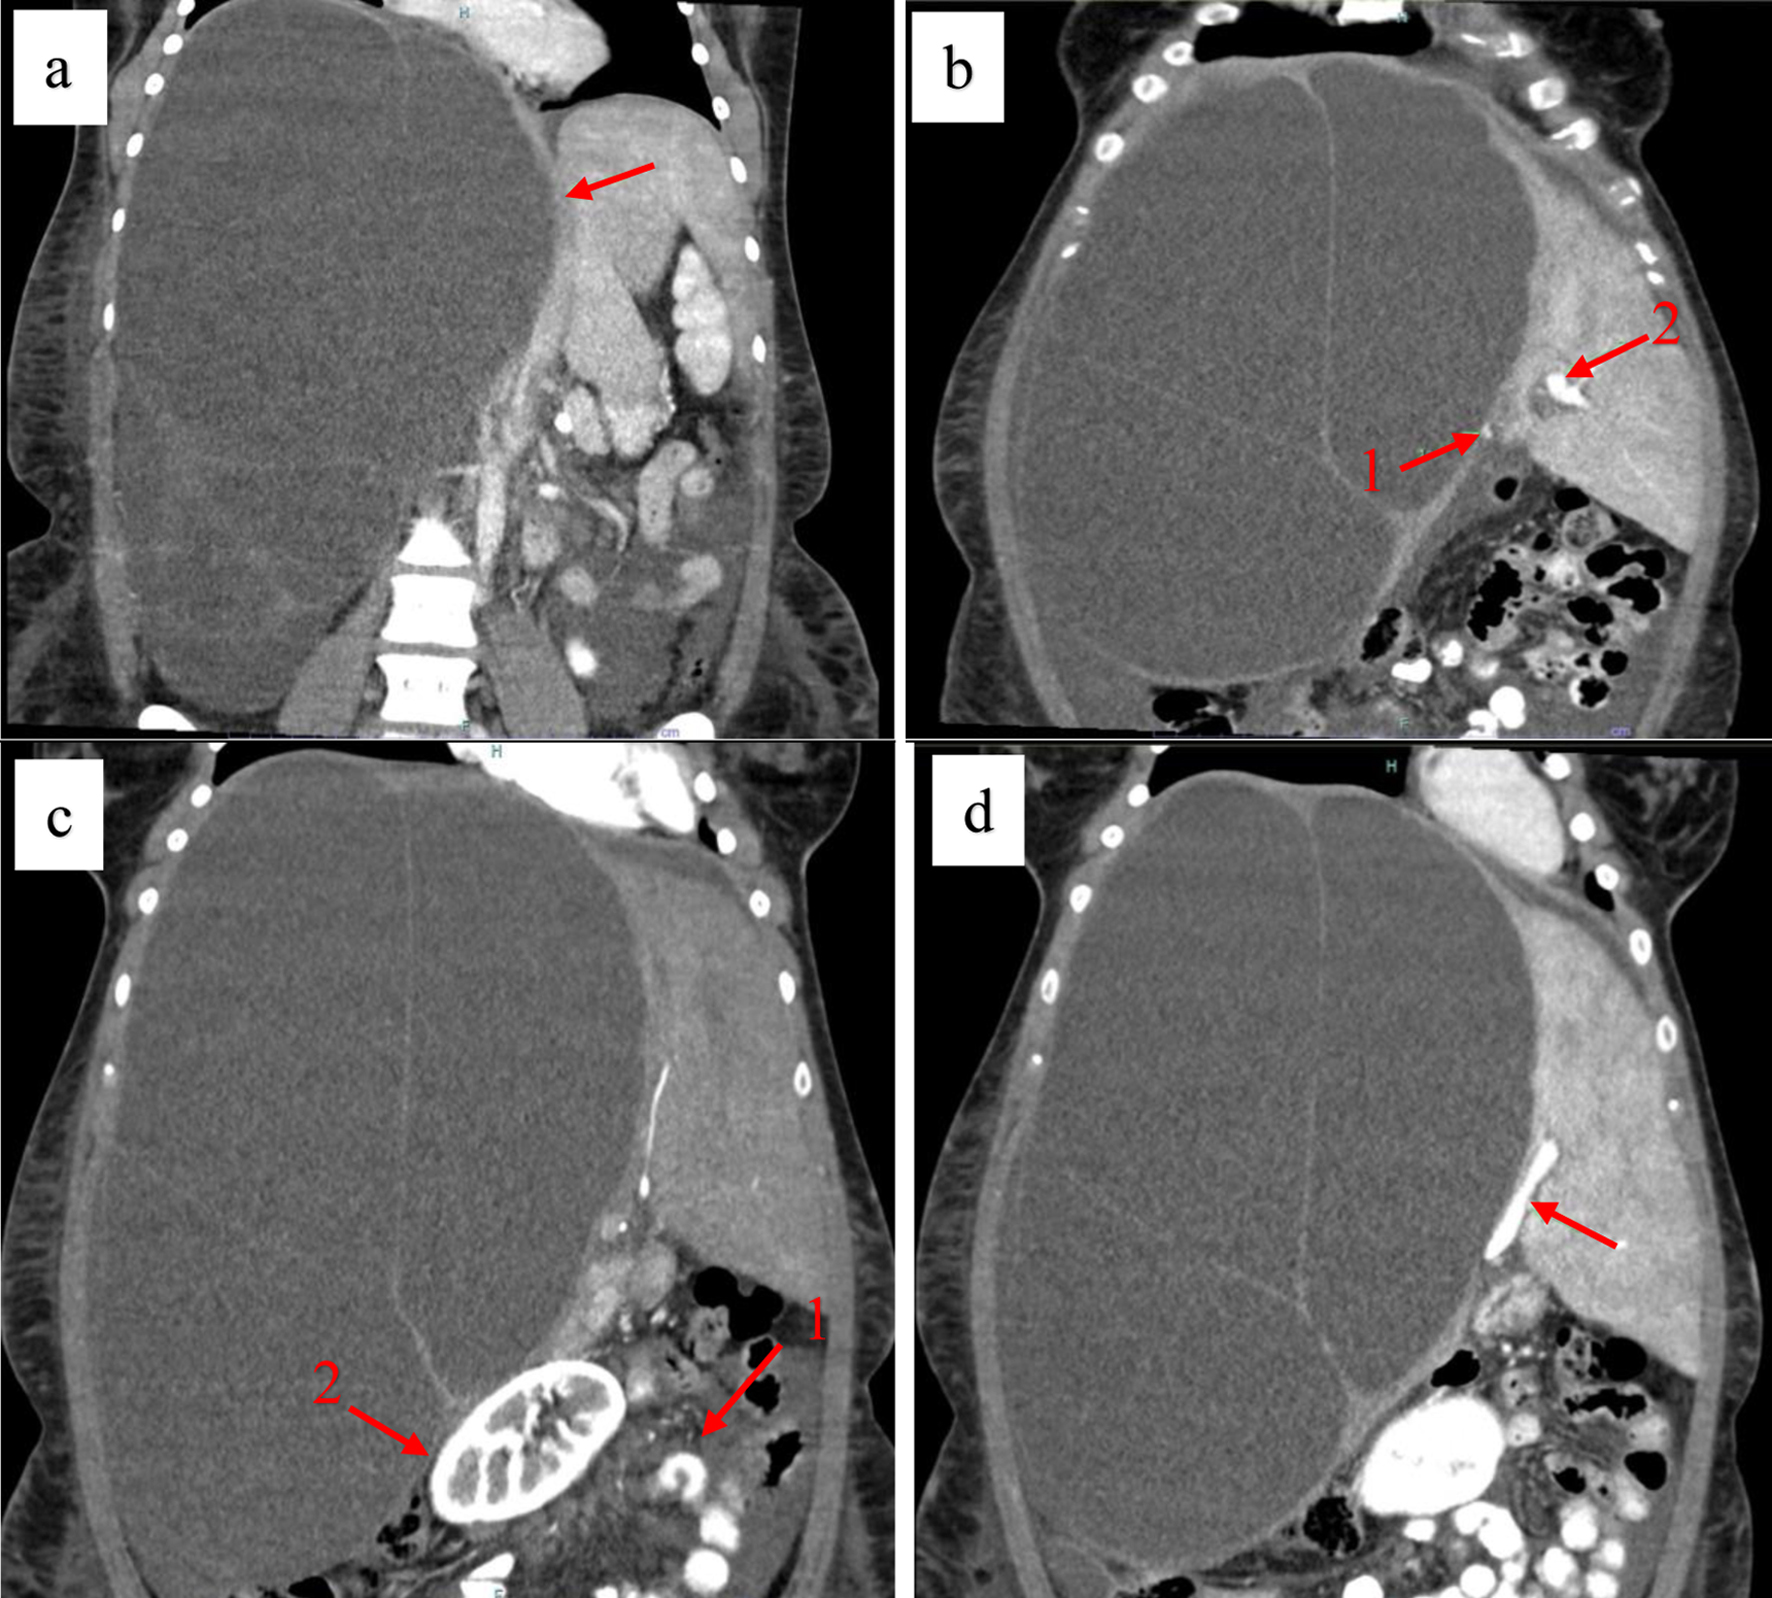

Abdominal computed tomography imaging with contrast revealed a massive, septated liver cyst in the right hepatic lobe measuring approximately 32 × 22 × 24 cm. The cyst had displaced the abdominal organs towards the left side of the abdomen and was associated with surrounding ascites. Furthermore, the inferior vena cava could not be traced to its entry into the right atrium, and the main right portal vein branch appeared significantly compressed (Fig. 2).

Figure 2. Coronal contrast-enhanced computed tomography (CT) scan showing a giant biliary mucinous cystadenoma. (a) Compression of the inferior vena cava (red arrow). (b) Compression of the left (arrow 1) and the right (arrow 2) portal veins. (c) Displacement of abdominal structures (arrow 1) and the right kidney (arrow 2) to the left. (d) Compression of the left portal vein (red arrow).